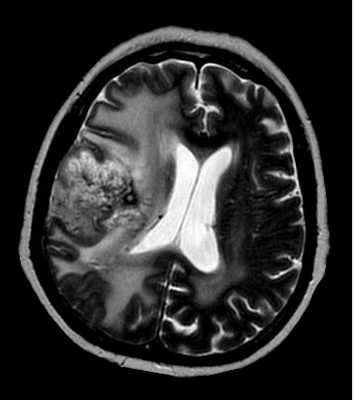

При МРТ головного мозга на Т2-зависимых МРТ выявляется узловое гиперинтенсивное образование, как правило, больших размеров, отек слабо выражен, границы нечеткие, структура неоднородная. Последнее связано с кальцификацией (50-90% случаев), кровоизлияниями, центральным некрозом и кистами. Контрастное усиление при МРТ наблюдается примерно в половине случаев, обычно при более злокачественных вариантах, особенно если контрастирование идёт по кольцевидному типу. Отличить олигодендроглиому от астроцитомы очень трудно. В пользу олигодендроглиомы говорят поверхностное расположение, кальцификация (доказывается с помощью КТ) и слабая выраженность отека при МРТ. МРТ в СПБ при опухолях мозга профессор Холин А.В. проводит преимущественно на разных типах МРТ. Среди центров МРТ СПб мы специализируемся нв выявлении различных опухолей.

МРТ головного мозга. Олигодендроастроцитома. Аксиальная Т2-зависимая МРТ.